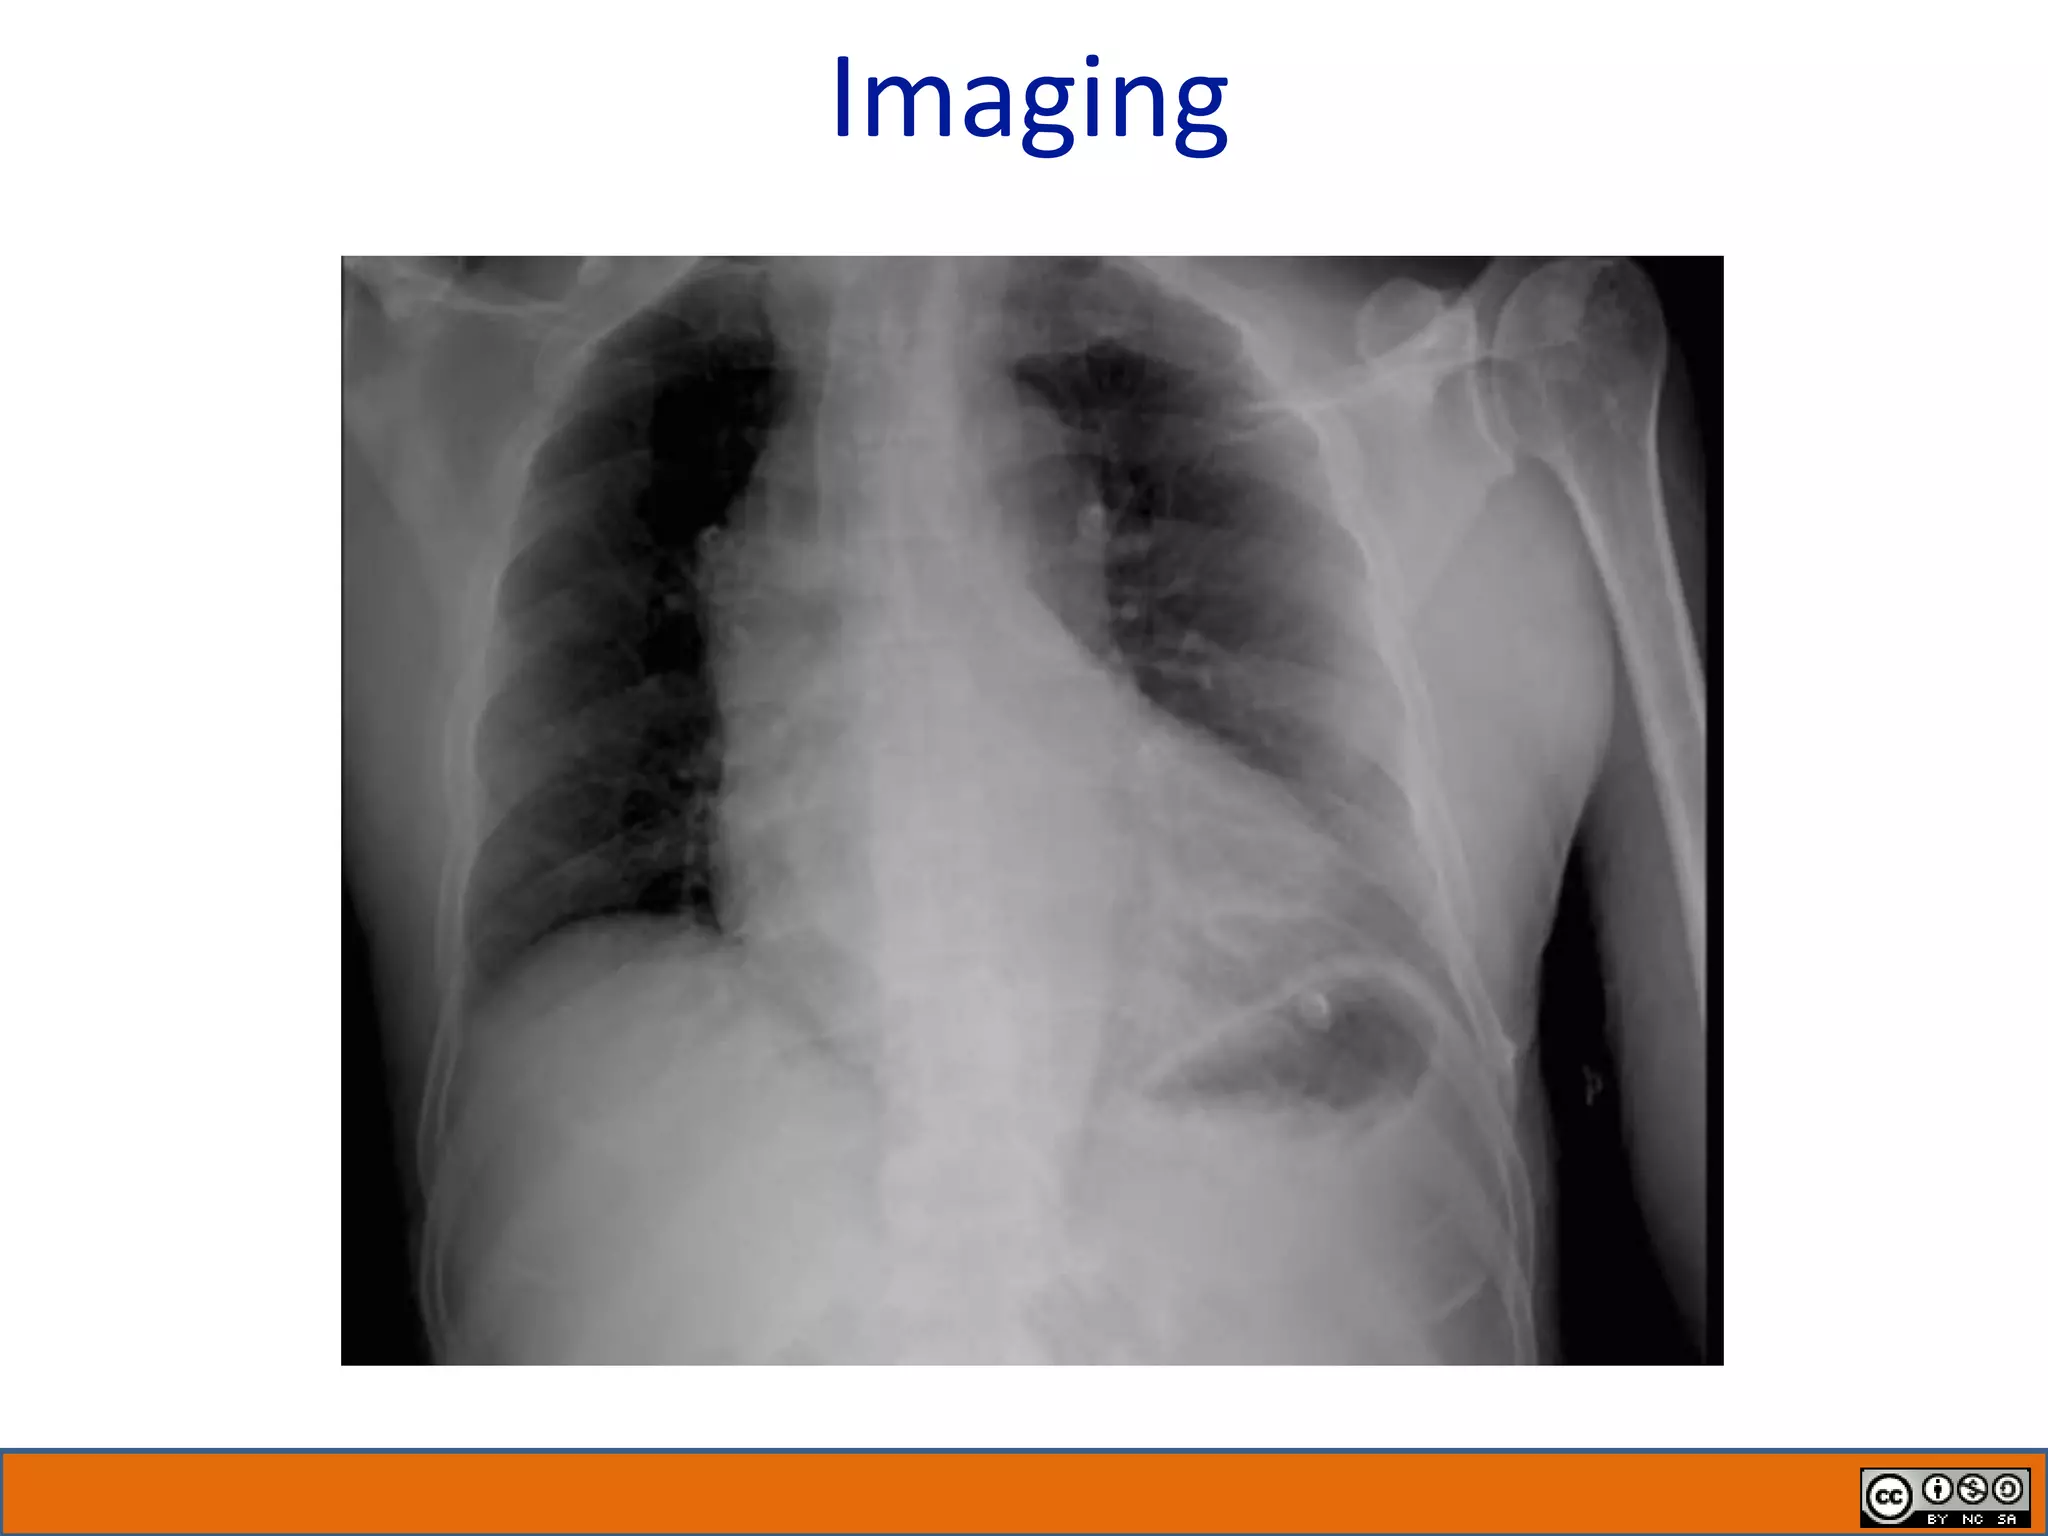

Imaging

• #11 Teacher’s guide: Invite a trainee to interpret the CXR Describe the non-con head CT results (demonstrated old lacunar infarcts in the bilateral basal ganglia) Key: Chest radiograph in the emergency department (portable) revealed clear lung fields, possible cardiomegaly, a tortuous aorta, and possible widened mediastinum.